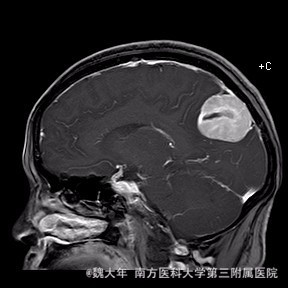

52岁,女性,因“反复头痛10余年,加重1年”入院。患者10余年前无明显诱因始出现头痛,表现为全头发作性胀痛,反复发作,无伴头晕、恶心,无呕吐、肢体抽搐,自行服药(具体不详)及休息后缓解,未予特殊处理。1年前患者觉头痛逐渐加重,以右顶部为甚,劳累或日晒后加重,无头晕、视物旋转,无恶心、呕吐,无发热、寒战,休息或平躺后症状稍有缓解,自行服药不能改善,至当地医院就诊,查颅脑MRI和CT提示“右侧顶部脑膜瘤”。

行“右顶开颅右顶部矢状窦旁脑膜瘤切除术”。取右顶马蹄形手术切口 ,颞侧翻开皮瓣,电刀切开骨膜,中线矢状缝上前、后极各钻一孔,颞侧后方钻一孔,铣刀铣一长方形(7*6cm)骨瓣,见硬膜表面较多点状渗血,予充分止血,悬吊硬膜。 显微镜下切除肿瘤:沿肿瘤边缘剪开硬膜后,见一大小约5*5*6cm肿瘤,沿硬膜内侧面呈匍匐状生长,边界与脑组织有蛛网膜分隔,质地较韧,基底与矢状窦关系密切,靠内侧与大脑镰粘连紧密,血供丰富。仔细分离肿瘤与脑组织的粘连,全切除肿瘤。肿瘤基底与矢窦粘连紧密,并破坏矢状窦侧壁,予低功率电刀反复烧灼,直至肿瘤无明显血供表现。严密止血后常规关颅。

术后1周复查头颅MR未见明显肿瘤残留,拆线后出院。